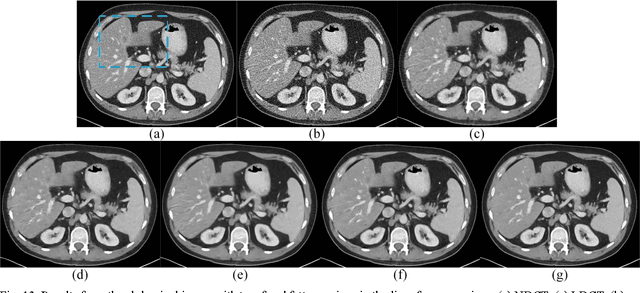

Abstract:Noise and artifacts are intrinsic to low dose CT (LDCT) data acquisition, and will significantly affect the imaging performance. Perfect noise removal and image restoration is intractable in the context of LDCT due to the statistical and technical uncertainties. In this paper, we apply the generative adversarial network (GAN) framework with a visual attention mechanism to deal with this problem in a data-driven/machine learning fashion. Our main idea is to inject visual attention knowledge into the learning process of GAN to provide a powerful prior of the noise distribution. By doing this, both the generator and discriminator networks are empowered with visual attention information so they will not only pay special attention to noisy regions and surrounding structures but also explicitly assess the local consistency of the recovered regions. Our experiments qualitatively and quantitatively demonstrate the effectiveness of the proposed method with clinic CT images.

Abstract:Given the potential X-ray radiation risk to the patient, low-dose CT has attracted a considerable interest in the medical imaging field. The current main stream low-dose CT methods include vendor-specific sinogram domain filtration and iterative reconstruction, but they need to access original raw data whose formats are not transparent to most users. Due to the difficulty of modeling the statistical characteristics in the image domain, the existing methods for directly processing reconstructed images cannot eliminate image noise very well while keeping structural details. Inspired by the idea of deep learning, here we combine the autoencoder, the deconvolution network, and shortcut connections into the residual encoder-decoder convolutional neural network (RED-CNN) for low-dose CT imaging. After patch-based training, the proposed RED-CNN achieves a competitive performance relative to the-state-of-art methods in both simulated and clinical cases. Especially, our method has been favorably evaluated in terms of noise suppression, structural preservation and lesion detection.

Abstract:To reduce the potential radiation risk, low-dose CT has attracted much attention. However, simply lowering the radiation dose will lead to significant deterioration of the image quality. In this paper, we propose a noise reduction method for low-dose CT via deep neural network without accessing original projection data. A deep convolutional neural network is trained to transform low-dose CT images towards normal-dose CT images, patch by patch. Visual and quantitative evaluation demonstrates a competing performance of the proposed method.